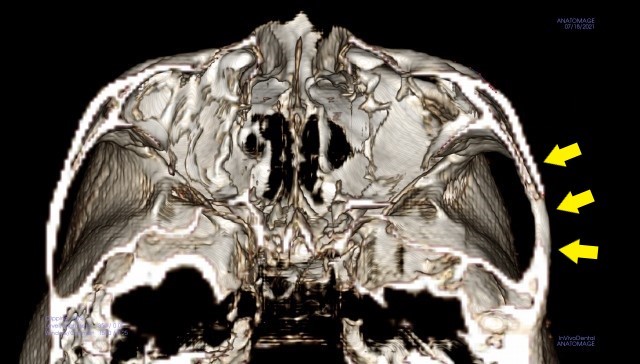

頬骨 痛いとき 急性上顎洞炎の治療

慢性上顎洞炎が、突然、急性化し、

顔が痛いし、頬骨も痛いほどの

急性上顎洞炎がおきました。

緑矢印 正常な上顎洞

黄矢印 膿がたまっている上顎洞

赤矢印 原因になった歯根

(上顎洞の底の骨が、溶けています)

仕事も休まれました。